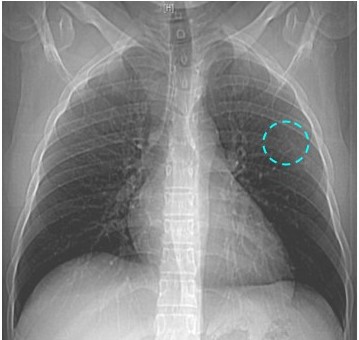

Paciente masculino de 30 años, quien consulta por presentar dolor en región dorsal izquierda, de tres meses de evolución, sin ningún otro acompañante. Al examen físico se constató dolor a la palpación en hemitórax izquierdo sobre el sexto (6o) arco costal posterior, sin alteraciones en la auscultación en ambos campos pulmonares. Se realizaron estudios de laboratorios que estuvieron dentro de los parámetros normales. Los estudios por imágenes como radiografía de tórax y TC evidenciaron; una imagen de defecto, localizada en el ángulo externo del sexto (6o) arco costal, en “pastilla de aspirina”, muy borrosa, de aspecto lítico con aparente abombamiento del periostio y pérdida de sustancia ósea, por lo que se recomienda realizar TC de tórax con ventana ósea y reconstrucción de pared torácica (Figura 1).

La tomografía multidectector, VCT64 de tórax con reconstrucción 3D, en donde se evidenció lesión única, ocupante de espacio la cual afectaba al sexto (6o) arco costal posterior izquierdo. Expansiva, con una porción central hipodensa de comportamiento osteolítico, con remodelación, adelgazamiento y expansión de la cortical, La lesión midió 16 mm x 36,4 mm x 17,5 mm, sin lesiones en los demás planos óseos. No se evidenciaron lesiones focales ni a nivel de la pleura o del parénquima pulmonar (Figura 2).